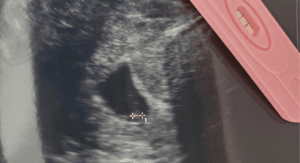

Miscarriage was not something that we spoke about in my family because it never really crossed our minds. I had a very healthy first pregnancy and delivered a chunky 8lb 11-ounce boy. About a year and a half later I decided to try for baby #2! I got pregnant on my 1st month of trying and everything seemed great.

At almost 9 weeks, I went to the restroom and saw blood. I went into a complete panic. It was a Sunday. I called my doctor and left a message. I knew exactly what was happening. My doctor called back and I will never forget her words, “It is what it is. If it is a miscarriage there is nothing you can do about it. I will see you on Monday.” How can she just brush it off? I was just talking about baby names 30 minutes ago and now my baby is gone.

4 months later, I was pregnant again. I remember being scared the whole time. Every time I would go to the bathroom, every time I would feel a little cramp, every time. Thankfully I was blessed with a healthy, tiny, 6lb 14-ounce baby girl.

In 2020, I was surprised by a very bright positive test. My 2 kids were ecstatic! They wanted a baby so badly. I was nervous but excited. Sadly, at 8 weeks, I started to bleed. This time was harder. This time I had a 6 and 3-year-old to explain it to. My heart broke for me and it broke for them.